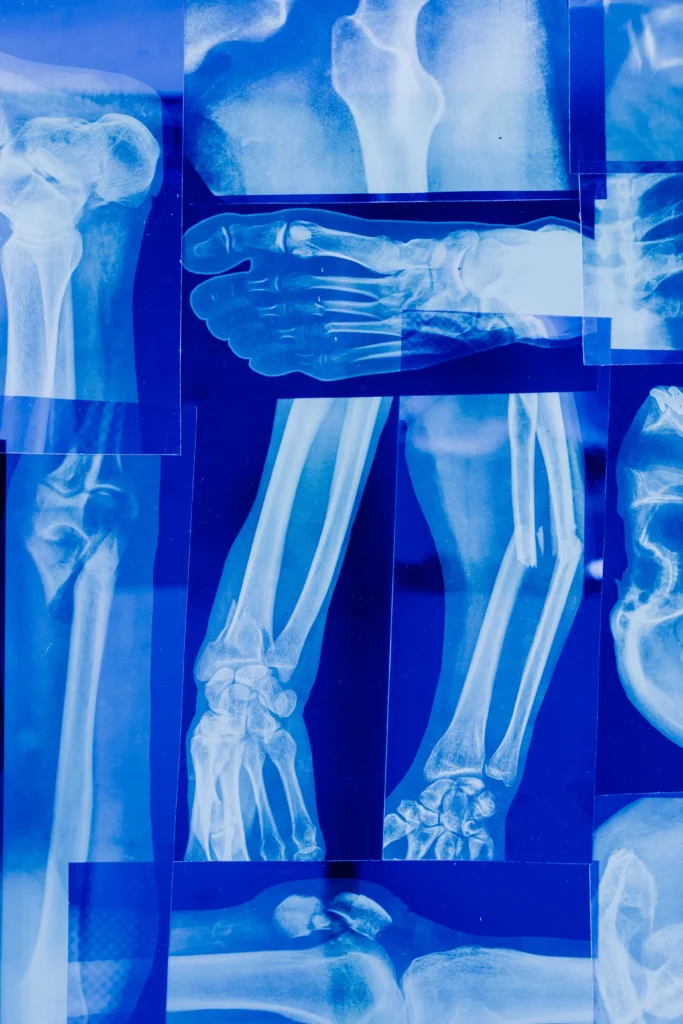

X선 검사: X선 사진을 통해 뼈의 밀도 변화나 약해진 부위를 확인할 수 있습니다.